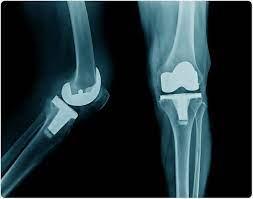

في هذا المنشور، سنتعرف على تشريح مفصل الركبة بوضوح من خلال الصور. سنتعرف على أجزاء الركبة ووظائفها، وكذلك أسباب وأعراض…

15 شهادات استبدال الركبة وشهادات المرضى في مركز هطيف للعظام والمفاصل body { font-family: Arial, sans-seri…

` مدونة عن الشهادات والآراء لاستبدال مفصل الركبة من خلال تجارب المرضى مدونة استبدال مفصل الركبة …

أفضل 15 قصة وتجارب لمرضى استبدال الركبة body { font-family: Arial, sans-serif; margin: 0; padding…